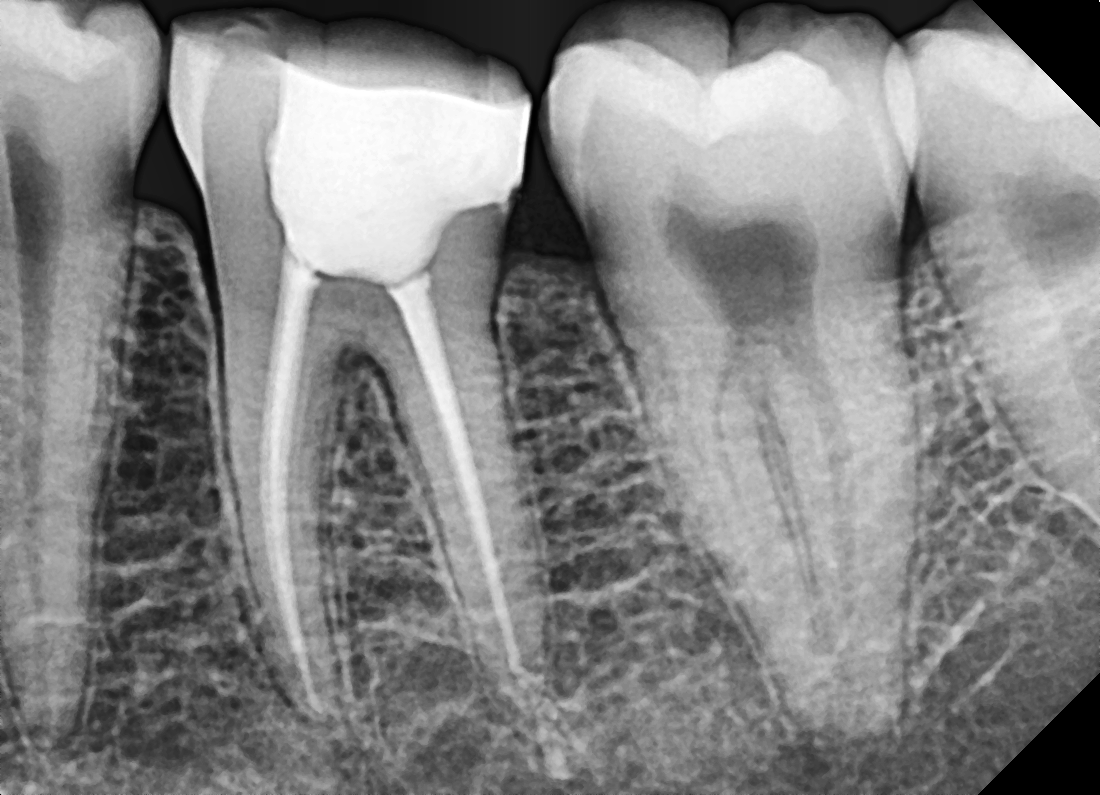

We begin with a thorough consultation, including digital X-rays, to assess the tooth. Our expert dentists will explain the problem and the treatment in detail, ensuring you’re comfortable and confident moving forward.

What we do: Using specialized tools, we access the inside of your tooth through a tiny opening. The infected or inflamed pulp is carefully removed.

What we do: The empty root canals are cleaned, shaped, and disinfected to eliminate bacteria.

What we do: The clean canals are sealed with a biocompatible material to prevent re-infection.

What we do: A temporary or permanent crown is placed to protect the tooth and restore its natural look and function.